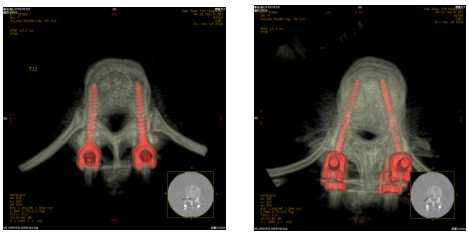

1、开展了从颈椎、胸椎、腰骶椎的椎弓根钉内固定和微创手术。